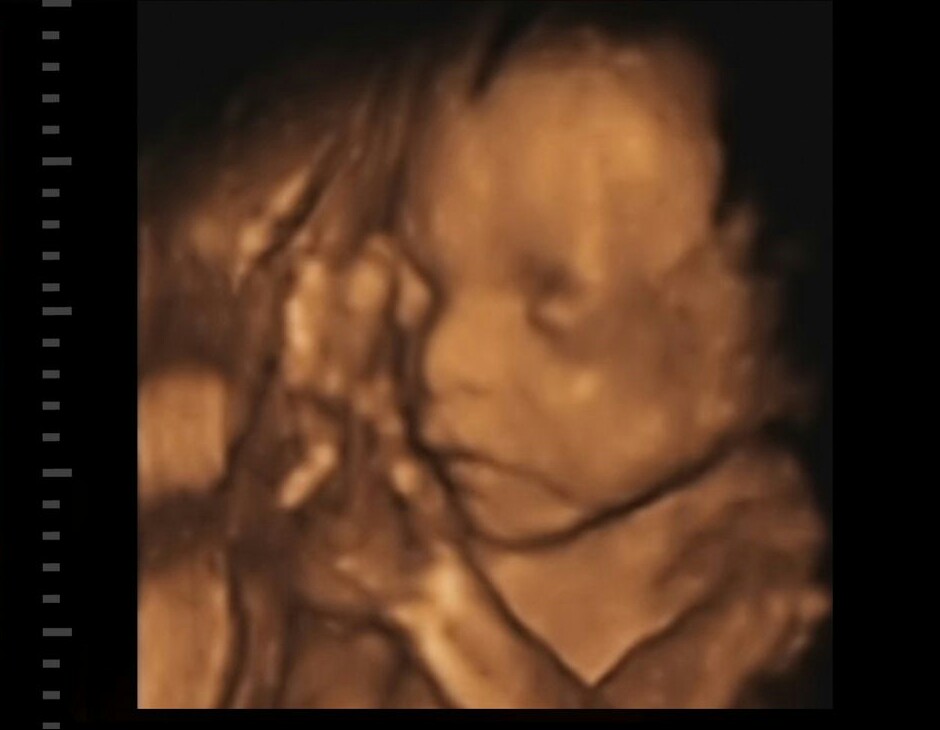

Naša malá Láska